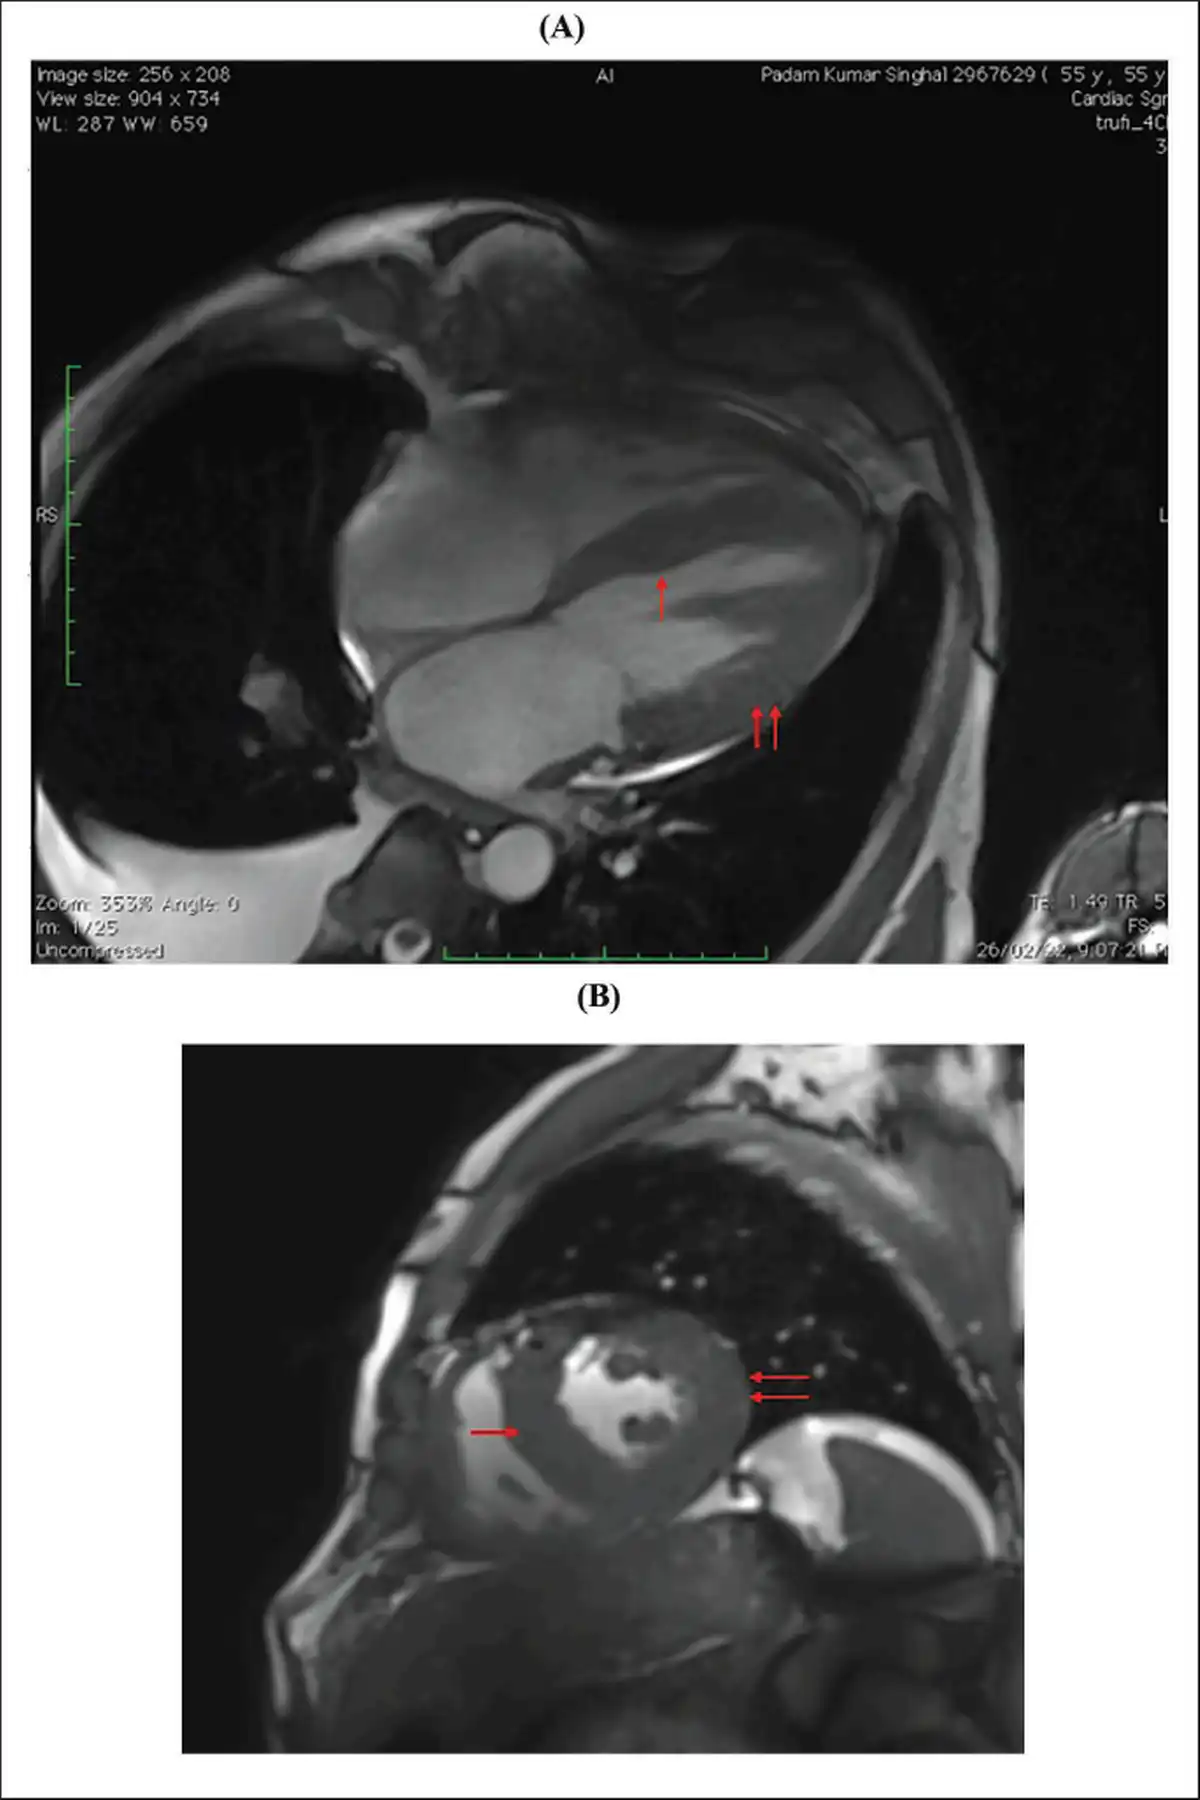

(A and B) Cardiac MR Showing Diffuse Thickening of Both Ventricles and Interventricular Septum (Red Arrows, Respectively).

Note: MR, magnetic resonance.

A clinical diagnosis of chronic congestive heart failure was made, and the patient was started on diuretics and investigated. Creatinine was 1.57 mg dl−1 with normal complete blood count and liver function tests (Table 1). Cardiac biomarkers revealed hs-tropI—383.7 ng l−1, Ck-MB—20 IU l−1, and NT-proBNP—8665 pg ml−1. Electrocardiogram (ECG) showed low voltage complexes in arm leads (Figure 1). Two-dimensional echocardiogram (2D ECHO) findings showed marked concentric left ventricular hypertrophy (LVH), LVEF—60%, abnormal global longitudinal strain pattern (apical sparing of longitudinal strain pattern), and cherry on top appearance. A low voltage ECG with concentric LVH and apical sparing of longitudinal strain pattern on 2D ECHO were suggestive of cardiac amyloidosis. A cardiac magnetic resonance (CMR) was done, which showed diffuse thickening of both ventricles, interatrial septum and interventricular septum, with reversal of the nulling pattern on T1 scout, with the diffuse enhancement of the walls of the thickened ventricles (Figures 2a,b and 3). A workup for primary amyloidosis was done. Serum immunofixation electrophoresis showed a monoclonal band in the beta region in the reference lane corresponding to lambda-only light chain, suggestive of light chain-only gammopathy (Figure 4). Free light-chain assay done showed involved FLC (lambda): uninvolved FLC (kappa) ratio was 14.01. iFLC was 835 mg l−1. dFLC was 775.39 mg dl−1. Serum B2 microglobulin was 5.39 mg l−1 (raised, cutoff—2.34 mg l−1). Total IgG was 14.06 mg l−1 (normal), IgA was 3.86 mg l−1 (normal), and IgM was 0.52 mg l−1 (normal). Flow cytometry immunophenotyping showed about 0.7% lambda-restricted abnormal plasma cells with reduced CD81 and aberrant CD28 expression. Bone marrow aspirate and biopsy were done, which showed trilineage hematopoiesis with myeloid preponderance and increased eosinophils and their precursors; plasma cells constitute about 5.5% of total nucleated cells with no evidence of amyloid deposit in the biopsy. A confirmatory diagnosis required a pericardial biopsy, but the patient refused for the same in view of the risk of adverse events. With cardiac ECHO/CMR findings and free light chain assay, a final diagnosis of AL-type cardiac amyloidosis, restrictive cardiomyopathy and heart failure with preserved ejection fraction (LVEF - 60%), on a background of chronic kidney disease, type 2 diabetes mellitus and hypertension was made. The patient was treated with intravenous Bortezomib (2 mg), Cyclophosphamide (300 mg) and Dexamethansone (40 mg). The patient showed clinical improvement and was discharged but was lost to follow-up.

Diagnosis of cardiac amyloidosis is often missed as it requires a high index of suspicion and low incidence overall. Laboratory tests, electrocardiography, cardiac imaging, and biopsy are required for making a diagnosis. Cardiac amyloidosis ECG pattern includes low voltage in limb leads (46%), due to electrically silent amyloid fibrils, and pseudo-infarct pattern (47%). Some ECGs may also depict arrhythmias, such as atrial fibrillation, AV blocks, and bundle branch blocks. Symmetric biventricular thickened wall with a spectrum of diastolic abnormalities (varying from abnormal relaxation to a restrictive filling pattern) is the hallmark of amyloidosis on 2D ECHO., , In cases where LV wall thickness is >12 mm without any history of hypertension, suspicion of cardiac amyloidosis should be kept high. Left ventricular ejection fraction is usually not affected till a later period in the disease course., As the longitudinal strain decreased on basal and mid-wall segments of the heart as compared to the apex, ECHO shows a pattern of apical sparing pattern, which is specific for cardiac amyloidosis. CMR is a better choice of investigation as it identifies the early stage of a diffuse subendocardial pattern of gadolinium enhancement and the late stage of transmural myocardial enhancement. These changes start to occur before the development of LVH., Mandatory investigations, in a patient with suspected amyloidosis, include serum and urinary protein electrophoresis and immunofixation to identify monoclonal protein., ,